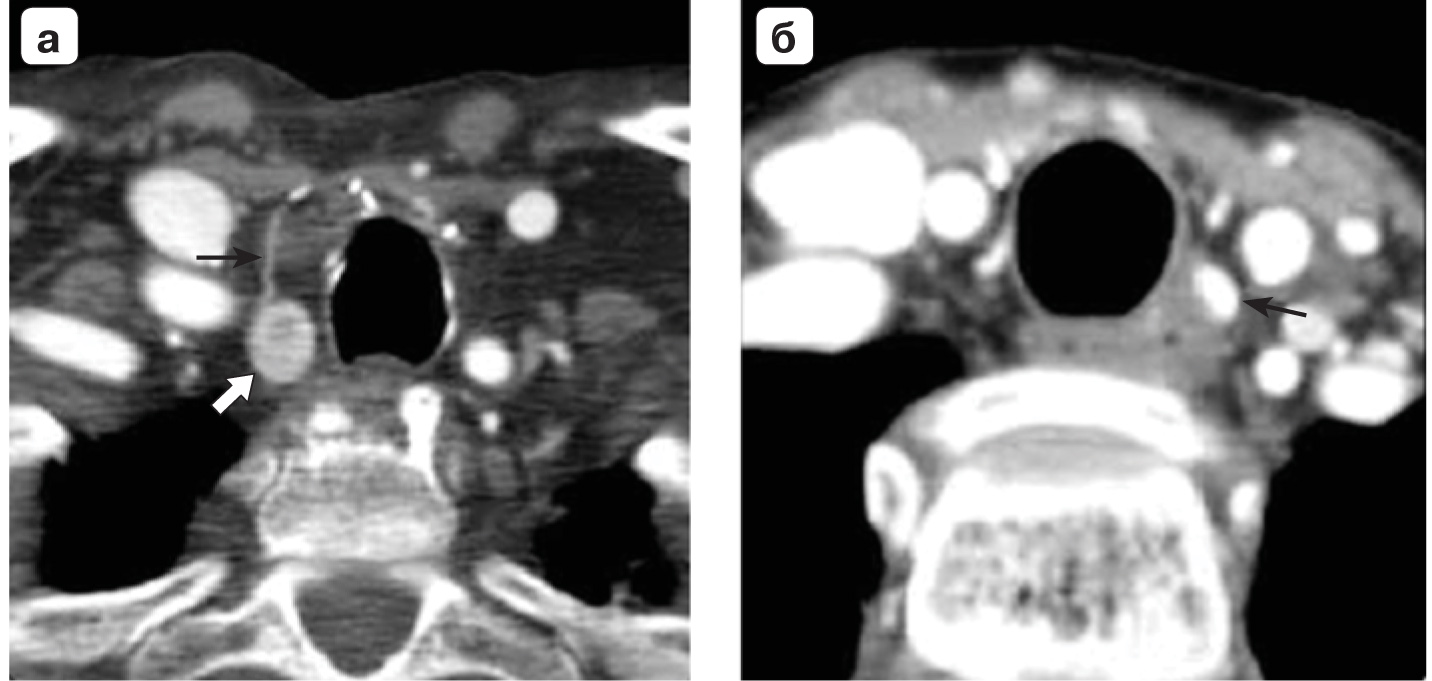

10. Fig. 9. Axial sections of CT with contrast; a - a typical picture of an artery (thin arrow) that supplies blood to the formation of the thyroid gland (thick arrow); b - the active formation of contrast-active thyroid gland, which, however, was poorly visualized in the delayed (venous) phase, almost corresponded in density to the esophagus (images from Diagnostic Imaging: head and neck, 3rd edition, Elsevier 2017). | |

| Subject | ||

| Type | Other | |

View

(206KB)

|

Indexing metadata ▾ | |